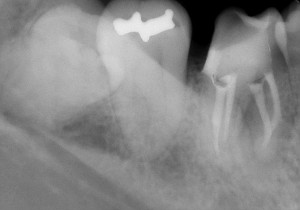

そこから中に折れ残っている破折器具と格闘すると・・・・

おお~っと出てきました! 2本しっかり除去しまして

そんなに長くはないのですが、これが行く手を阻んでいました。

その後は、いろいろな器具を使いながらエンヤ~コ~ラ~と進めていくと・・・

こんな感じに無事終了することが出来ました。結構曲がりくねった神経の通り道ですね~。

その後は、土台と仮歯を入れて経過観察させていただきました。

その後は、症状も特になく経過良好であることからかぶせ物を入れて終了となりました(^0^)/

終了時はこんな感じ!